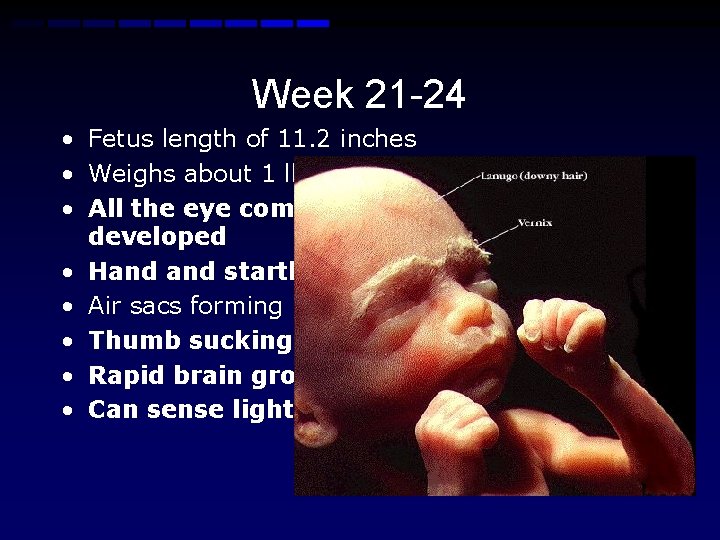

Week 21 -24 • Fetus length of 11. 2 inches • Weighs about 1 lb. 10 oz. • All the eye components are developed • Hand startle reflex • Air sacs forming in lungs • Thumb sucking • Rapid brain growth • Can sense light/sound